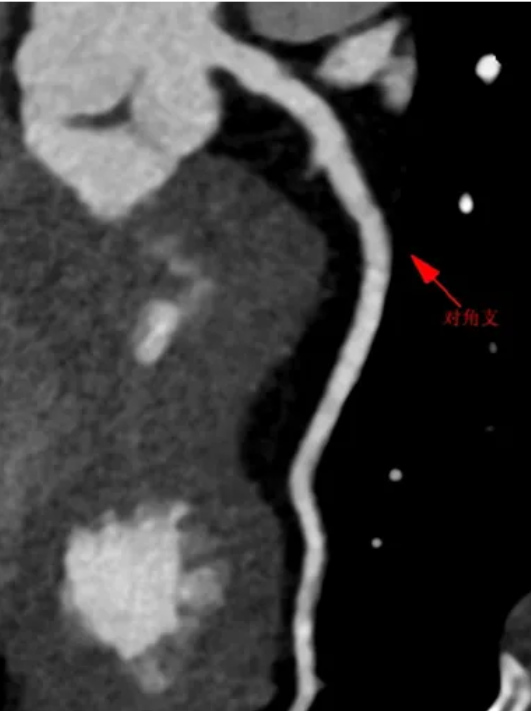

王阿姨最终还是抵挡不住反复胸闷,在家人陪同下,她来到上海德达心血管医院心内科就诊。接诊医生详细查看病历、询问病史后,凭借丰富的临床经验,初步怀疑她存在冠状动脉狭窄,建议通过冠脉造影进一步明确诊断。作为冠心病诊断的 「金标准」[1],冠脉造影技术通过向冠状动脉注入造影剂,配合 X 线透视,能够清晰呈现血管形态、狭窄部位及程度,即便是微小病变也无所遁形。果然,检查结果显示,王阿姨的前降支出现重度狭窄,狭窄程度高达 90%。这意味着心脏的 「生命通道」 几近堵塞,随时可能引发心肌梗死,危及生命安全。

为制定更精准的治疗方案,专家团队引入血管内超声(IVUS)技术进一步评估。IVUS 如同医生的「血管显微镜」,通过导管将微型超声探头送入血管,能清晰呈现血管壁结构及斑块性质。检查发现,王阿姨前降支狭窄处布满脂质斑块——这类斑块质地软、不稳定,极易破裂形成血栓,正是引发急性心血管事件的「定时炸弹」 。

结合冠脉造影与 IVUS 结果,专家团队确定:必须立即介入治疗,开通血管,同时强化降脂,消除斑块隐患!在介入手术中,医生精准操作,通过切割球囊扩张,管腔恢复满意,予以药物球囊扩张,恢复前降支血流;术后,心内科专家为她制定了严格的降脂方案,反复强调:「他汀不仅要吃,更要长期规范服用!它能降低血脂、稳定斑块,把『软趴趴』的危险脂质斑块变成『硬石头』,减少破裂风险。」